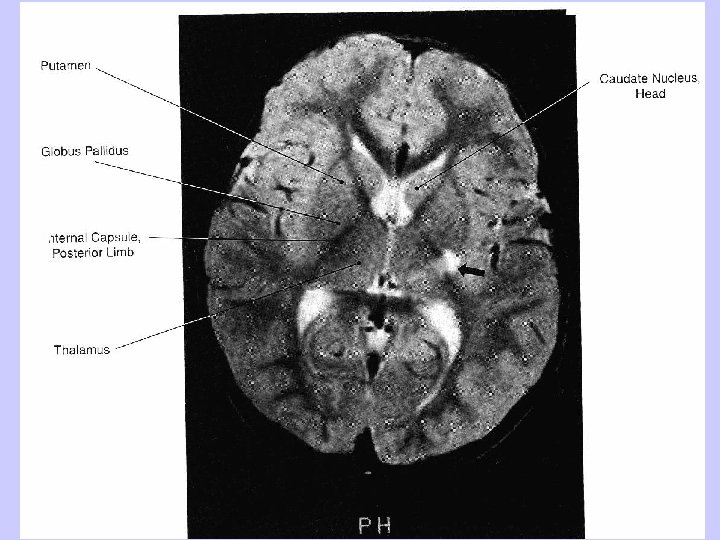

Recurrent Artery of Heubner (Medial Striate Artery) Syndrome Infarction in the territory supplied by the recurrent artery of Heubner (medial striate artery), which is a branch of the anterior cerebral artery, results in the following signs: 1. Contralateral face and arm weakness without sensory loss 2. Behavioral and cognitive abnormalities, including abulia, agitation, neglect, and aphasia The clinical signs reflect involvement of the anterior limb of the internal capsule, rostral basal ganglia (caudate nucleus and putamen), and the basal frontal lobe.

Anterior Choroidal Artery Syndrome Occlusion of the anterior choroidal artery, a branch of the internal carotid artery, may be asymptomatic or may result in one or more of the following: 1. Contralateral motor deficit (hemiplegia) involving the face, arm, and leg due to involvement of the posterior part of the posterior limb of the internal capsule and the cerebral peduncle. This is the most consistent and persistent deficit. 2. Contralateral hemisensory deficit, usually transient, involving, in most cases, all sensory modalities (hemianesthesia) due to involvement of the sensory tracts within the posterior limb of the internal capsule. 3. Contralateral visual field defect (hemianopia or quadrantanpoia) due to involvement of the retrolenticular part of the internal capsule (visual radiation) or the lateral genticulate nucleus. This is the most variable feature of the syndrome.

Lenticulostriate Artery Syndrome Infarction in the territory of the lenticulostriate artery, a branch of the middle cerebral artery, is associated with pure motor hemiplegia because of involvement of the internal capsule.